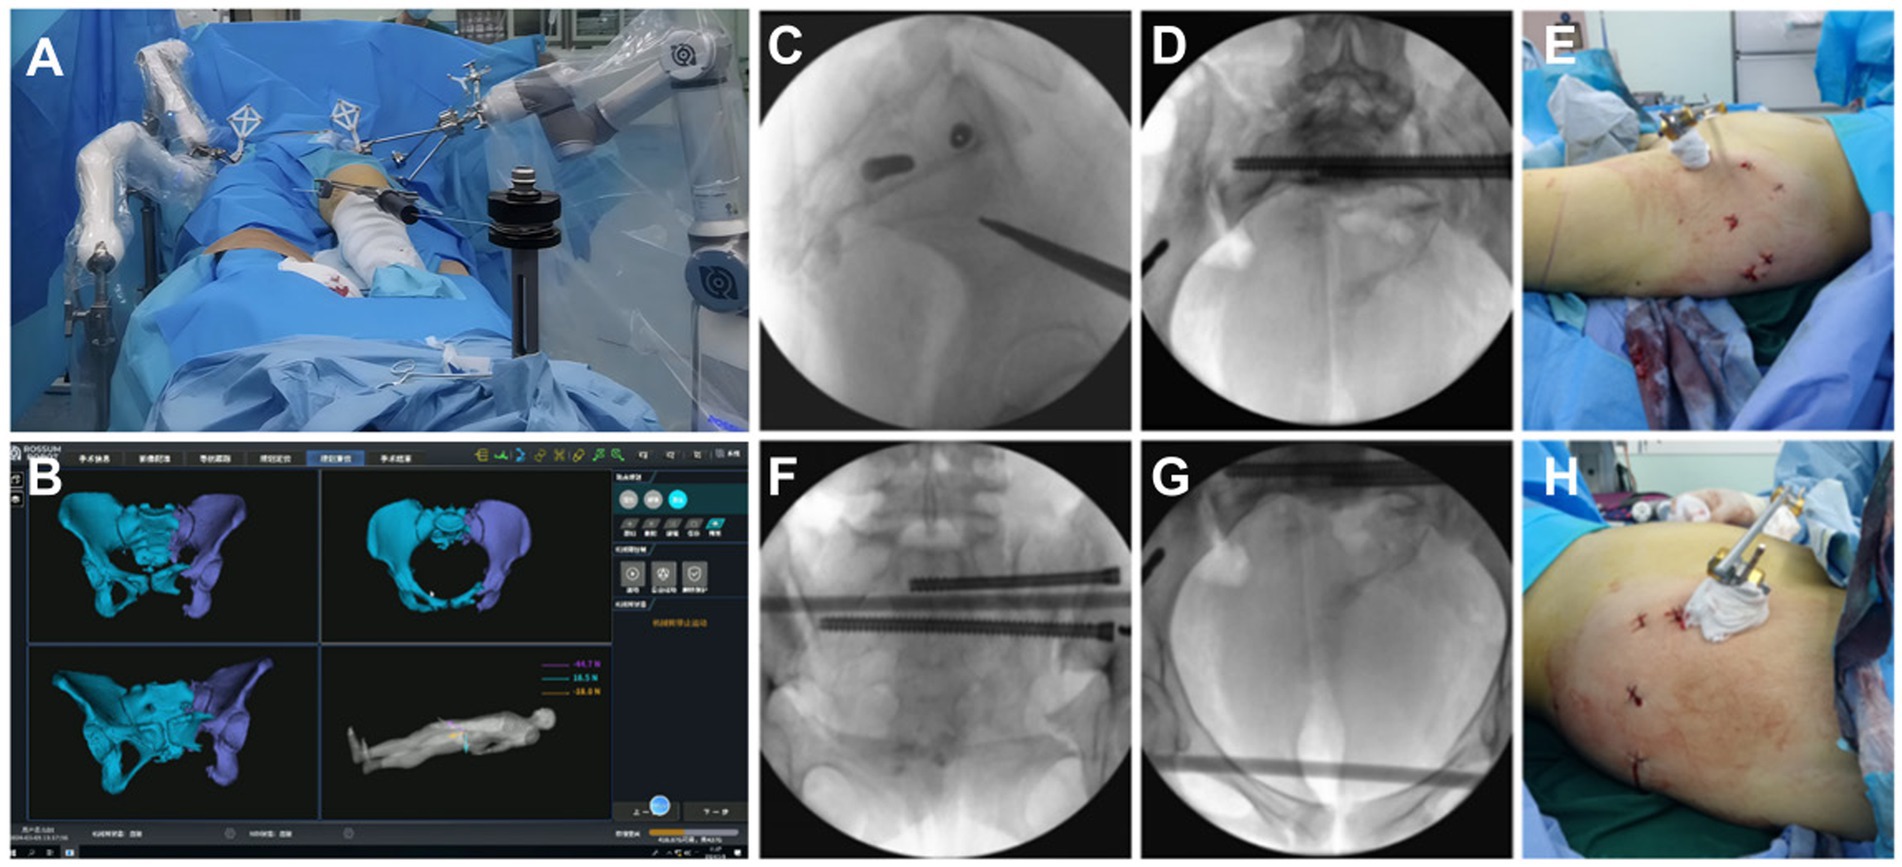

4.1.2 Surgical procedure

The patient was positioned supine under general anesthesia, with the hip elevated for better access.

Following the intraoperative layout, the holding arms were connected, and standard disinfection procedures were carried out.

The patient and robotic trackers were securely installed, CBCT data were collected, and image registration was performed.

Using navigation drilling, Schantz pins were placed under guidance to ensure pelvic stability.

Femoral traction was applied, and the robotic arm moved the pelvis along the planned path to the target position.

After achieving reduction, appropriate implants were selected to stabilize the pelvic structure.

X-rays were taken before the conclusion of the procedure to verify accurate reduction and correct screw placement.

The surgical procedure is shown in Figure 4.

Figure 4

(A) A connection was established between the five Schantz pins and the holding device, and the femoral condylar traction pin was linked to the elastic traction device. (B) Under real-time 3D navigation, the robotic arm autonomously moved the affected hemipelvis along the pre-planned reduction path, achieving autonomous reduction. (C–H) AII screw channels were verified by fluoroscopy, and the results were satisfactory. The wound appearance was minimally invasive.